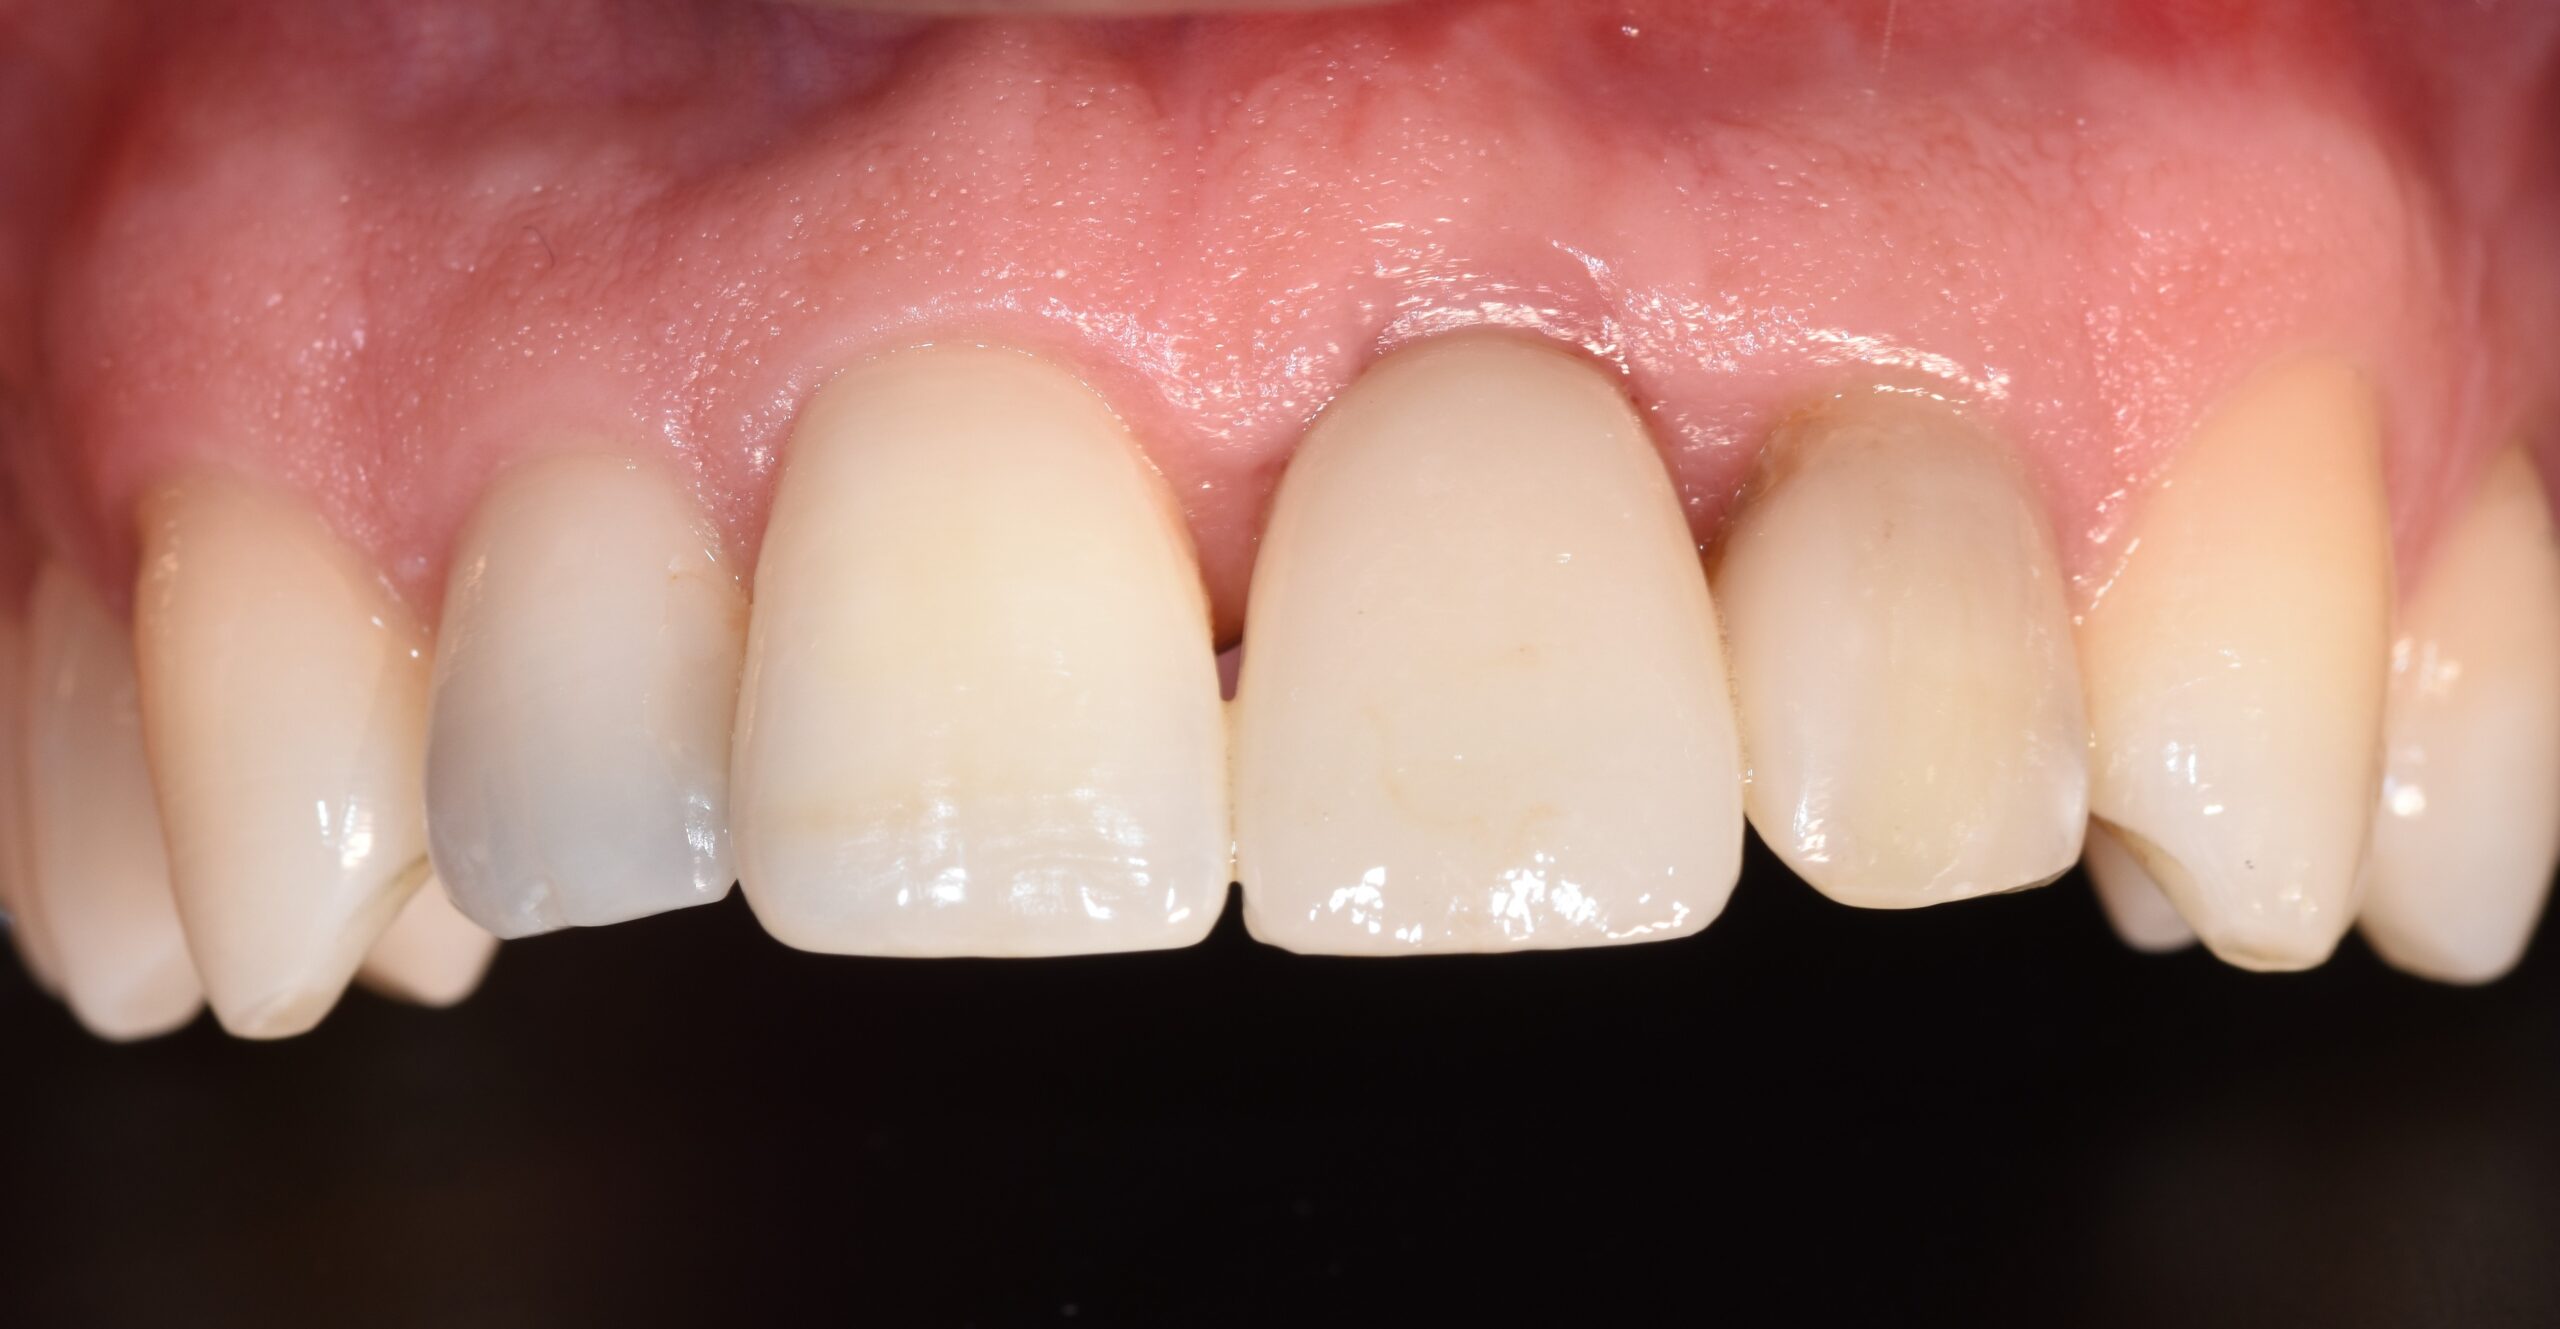

Dopo ulteriori tre mesi, l’impianto veniva testato con accesso “flapless”; accertata la sua osteointegrazione con il metodo dello svitamento della vite tappo, veniva predisposto un provvisorio avvitato previa impronta ottica, con indicazioni precise riguardo il profilo di emergenza, che veniva riverificato e corretto direttamente sul paziente seguendo la morfologia dritto/concava della porzione emergente dalla interfaccia implantare (spazio subcritico) per circa 2 mm; a seguire, lievemente divergente coronalmente per circa 2,5 mm (spazio critico) (17) avendo cura di non superare l’angolazione massima di 30°18. Tali indicazioni limiterebbero il riassorbimento del margine crestale osseo, preservando i volumi tissutali (Figura 11).

Il provvisorio veniva lasciato a dimora per altri due mesi per consentire la stabilizzazione dei tessuti e del loro profilo per poi procedere con il restauro finale in zirconio-ceramica (Figura 12).

A distanza di sei mesi dall'applicazione del restauro definitivo i tessuti apparivano stabili, con mantenimento della morfologia pre-terapia (Figura 13).